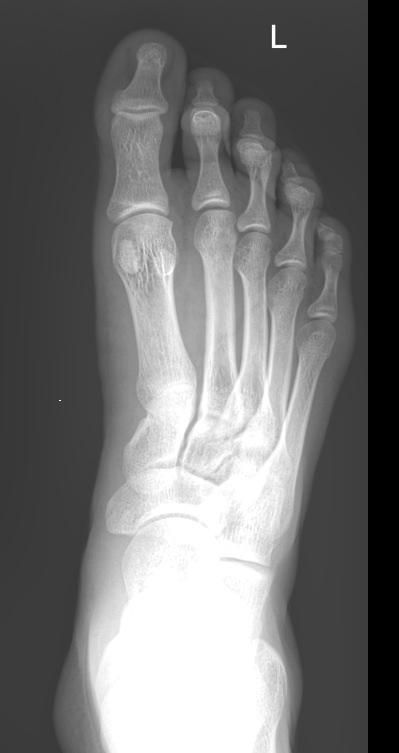

В качестве диагностической процедуры для выявления плоскостопия часто используют рентген. Прицельное исследование стопы позволяет увидеть изменения в ее строении, а также вычислить угол и высоту свода стопы, показатели которых используются для установления стадии болезни.

Что покажет рентген стопы на продольное плоскостопие

На снимке будут отчетливо видны:

• Кости предплюсны;

• Наложенные друг на друга кости плюсны;

• Травмы, в том числе застарелые;

• Патологические изменения видимых суставов;

• Опухоли.

Рассчитывается высота и угол свода стопы и соответствующая им степень плоскостопия.